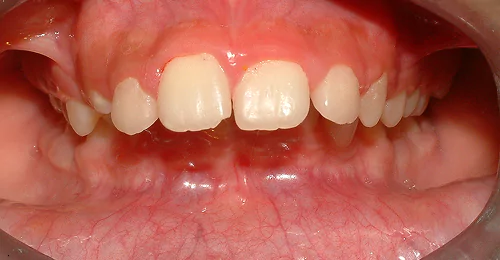

Anterior Crossbite Correction

Without Extraction Of Teeth

A young newly married female had crossbite in front teeth and when she smiled she felt her teeth appeared crooked. Being newly married she also had concerns regarding wearing braces. Assessing the situation, we advised ceramic braces and treated the condition without extracting or removing any teeth.

Pre Treatment

The treatment was completed successfully after a period of 18 months. Our patient is now embarked on her newly married life with more confidence.